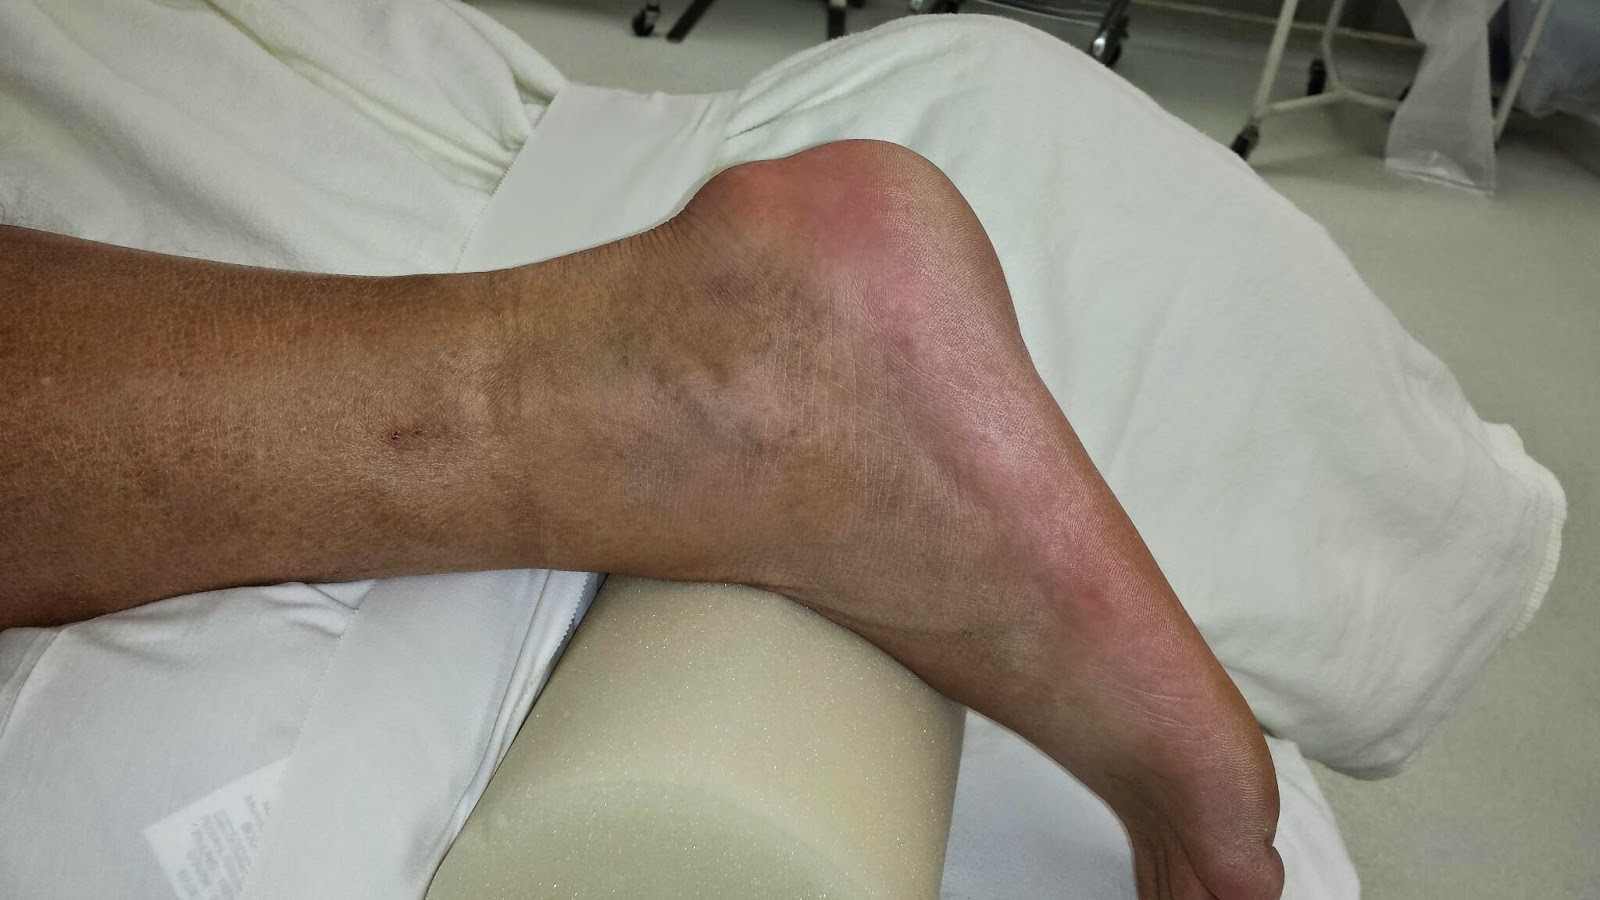

临床上,后撞击综合征表现为踝关节后慢性疼痛和肿胀。典型的是,这种情况在导致足底极度跖屈的活动中出现,如芭蕾舞、足球、橄榄球和下坡跑。

(1)急性足底过度屈曲损伤和(2)慢性重复性微创伤。这两种机制的相似之处在于后部软组织,后者可能在距骨后和跟骨之间继发性肥大和压缩。骨体的存在(距后三角骨(OT)和Stieda突)会进一步缩小这个空间,这导致了它的另一个名称“距后三角骨综合征”(图12)。51这种增生的压迫导致区域肌腱和韧带的损伤。拇长屈肌腱鞘炎通常受累(图12)。重要的细分包括跟腱肌病/撕裂、关节病、急性距骨后突骨折、拇长屈肌腱鞘炎、Haglund综合征、骨软骨损伤和跟骨后滑囊炎。